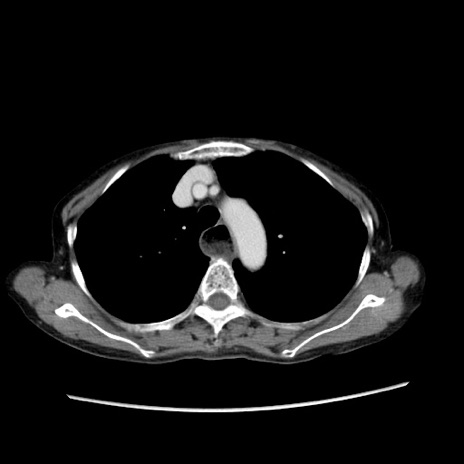

症例25(横断像)

【症例】80歳代女性

【主訴】胸のつかえ感

【現病歴】約9時間前に食後から胸のつかえた感じあり、嘔吐あり、来院。

【既往歴】胃癌(全摘)、胆摘、虫垂炎

【身体所見】心窩部に圧痛あり、反跳痛なし。

【データ】WBC 5700、CRP 0.05